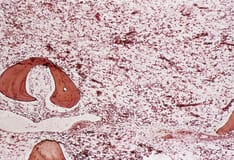

Microscopic examination of the peripheral blood smear is indicated to confirm lymphocytosis. It usually shows the presence of smudge cells, depicted in the image below, which are artifacts from lymphocytes damaged during the slide preparation.

Peripheral smear from a patient with chronic lymphocytic leukemia, large lymphocytic variety. Smudge cells are also observed; smudge cells are the artifacts produced by the lymphocytes damaged during the slide preparation.